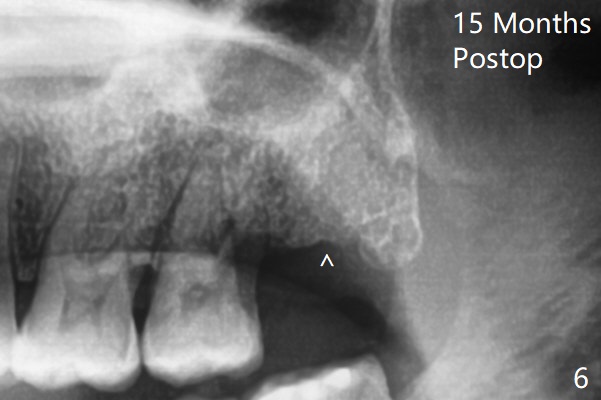

The bone density is high post #1 extraction (Fig.6 (left panel)), related to difficult removal (DB root tip fracture). It appears that bone graft at #16 (^) remains in place 15 months postop.